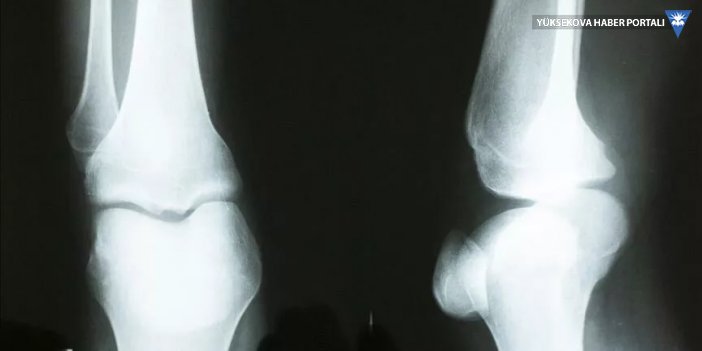

Herhangi bir gerekçe ile kişinin kemik yaşı tespiti gerektiğinde el bilek görüntüsü sisteme yüklenerek, bir dakikanın altında sürede tespit yapılabilecek.

Bu kapsamda akademisyenler Özdemir ve Gedik ile yaptıkları çalışmada kemik yaşı tahmini için radyologların iş akışını hızlandıracak bir çalışma yürüttüklerini ifade eden Kaya, sol el bilek grafisinden derin öğrenme teknolojisi kullanılarak bilgisayar temelli bir karar destek sistemi geliştirdiklerini belirtti.

Verileri Kütahya'daki 4 hastaneden elde ettiklerini dile getiren Kaya, "Yapay zeka tekniklerini kullanarak el grafilerinden kişinin yaşını tespit etmeye çalıştık. Yaş tespiti çok zahmetli bir şekilde radyologlar tarafından belirleniyor ama bilgisayar sistemiyle çok daha kolay ve hızlı şekilde gerçekleştirebilirsiniz" dedi.

Kaya, el grafisinden kemik yaşı tespitinin daha önce yaklaşık 2 saat sürdüğüne işaret ederek, geliştirdikleri sistemle yaş tespit süresinin saniyelere düştüğünü kaydetti.

Öğretim görevlisi Cüneyt Özdemir de derin öğrenme yöntemiyle sol el bilek grafisinden kemik yaşı tespitine yönelik çalışmaların 18 yaş altı ve 18 yaş üstü bireylere yönelik iki aşamadan oluştuğunu belirtti.